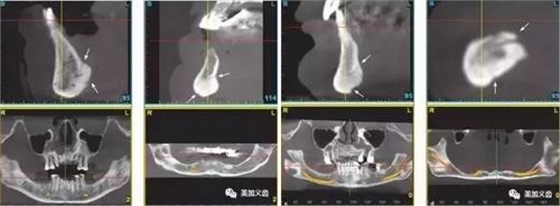

5、術(shù)前一定要拍CT,研究植入位點(diǎn)解剖結(jié)構(gòu)。

1、舌下動(dòng)脈分支可通過(guò)副舌孔進(jìn)入前磨牙或前牙區(qū)下頜骨(中線(xiàn)處較多見(jiàn))。

4、無(wú)牙頜患者牙槽骨嚴(yán)重吸收者,舌頦動(dòng)脈離牙槽嵴頂近,種植體植入易傷及舌頦動(dòng)脈。